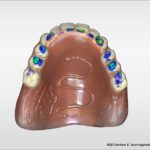

Here the lab can take this information and transfer it to the denture design software. In this case 3Shape Dental Studio was used. The overlay is used to ‘set’ the denture teeth at the new position to allow more tooth to show at rest and at smile.

The final denture design was completed in the software. The lower teeth were intruded to not create excessive overbite.